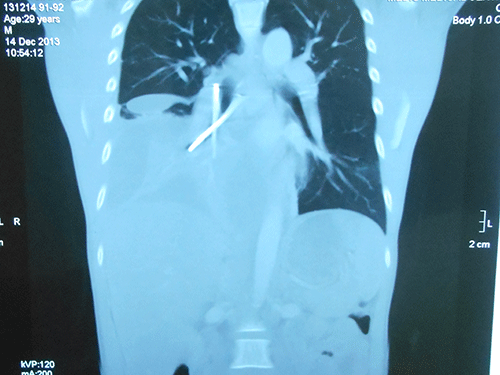

| Hai cây đinh trong bụng bệnh nhân B. Ảnh: Do bệnh viện cung cấp |

Qua các xét nghiệm máu cần thiết, chụp CT 64 lát cắt ở ngực, bụng, các bác sĩ tại BV Hoàn Mỹ Sài Gòn đã phát hiện bệnh nhân bị tràn dịch màng phổi phải lượng nhiều, tạo khoang, dị vật dạng 2 cây đinh bắt chéo chữ X trong phế quản trung gian phổi phải.